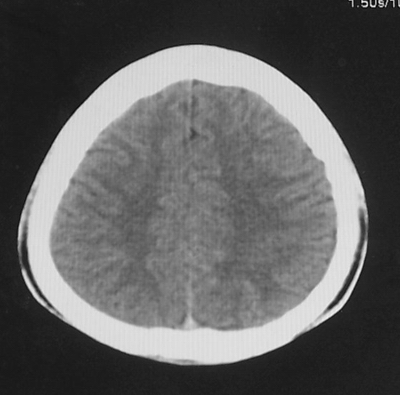

患者、男、18y,头痛5天入院。

左小脑、右丘脑区低密度影,无明显强化及占位表现,男18y,先考虑脑部炎性病变,如脑炎、血行播散性感染等,建议结合临床如脑脊液检验。

左侧小脑半球低密度影,占位不明显,但不能排除肿瘤,我诊断胶质瘤,脑炎及脑梗临床不符.

左侧小脑半球及右丘脑低密度影,考虑脑梗塞可能.

单独看左侧小脑半球的不规则形囊性低密度灶,从发病部位、年龄以及无强化、无占位效应的特点可以考虑毛细胞瘤型星形细胞瘤。同样,如果单独看右侧丘脑的近圆形低密度,也可以考虑囊变形星形细胞瘤。只是胶质细胞瘤一般为单发直接浸润、蔓延生长,而不是在脑内同时出现多个病灶,且瘤周没有一点儿水肿,暂时不予以考虑。

脑炎倒是首先可以考虑,只是临床症状、病史不很符合,建议狼兄仔细了解病史以及其他临床资料。

同时,现在已经进入冬天,一氧化碳中毒也需要考虑进去。不知道增强是什么时间做的,与平扫间隔几天?如果中间时间比较久而且进行吸氧等治疗,则平扫所示右侧颞叶密度比较低、右侧小脑半球以及脑桥也似有片囊状低密度,但在增强却没有发现就可以比较合理的解释了。

左侧小脑半球及右丘脑低密度影,考虑炎症可能性大

左侧小脑半球及右丘脑低密度影,考虑  1、脑梗塞灶. 2、占位性病变,建议作mri检查